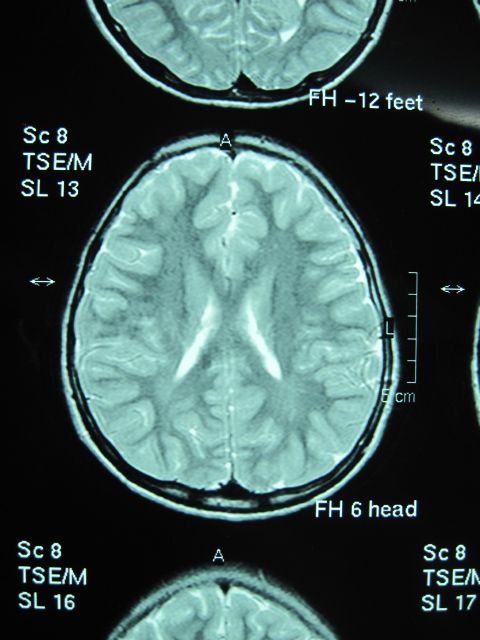

Brian MRI

انجام شد که تصویر کلیشه ضمیمه است.

تشخیص شما چیست ؟